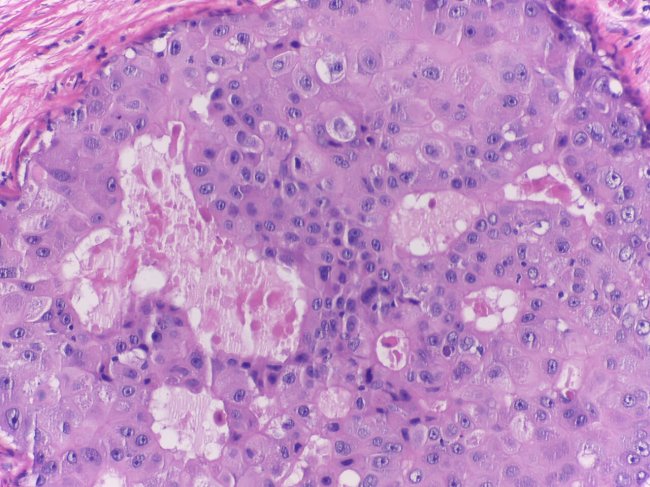

• Anatomia Patológica

Nos casos em que há lugar a tratamentos farmacológicos, garantimos o acesso aos fármacos mais inovadores, assegurando um tratamento médico personalizado, à base de Quimioterapia, Hormonoterapia e Imunoterapia, de acordo com o comportamento das células tumorais, avaliadas em estudo imunohistoquímico pela Anatomia Patológica e, de acordo, com as características da doente.